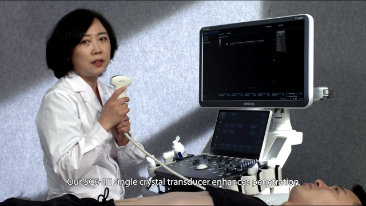

Zorg met minder stethoscoop, meer echografie?

Geoptimaliseerde workflows in gynaecologie en verloskunde zijn noodzakelijk ter ondersteuning van grote pati?ntenvolumes aan screeningbezoeken voor vrouwen. Misvormingen van het centrale zenuwstelsel (CZS) zijn bijvoorbeeld een van de meest voorkomende aangeboren afwijkingen. Als gevolg van verschillende beeldvormingscondities, zoals een slechte foetale positie, is de MSP zeer moeilijk te vinden in een 2D-echografie. Daarom kunnen geautomatiseerde detectie en metingen de scaneffici?ntie sterk verbeteren.